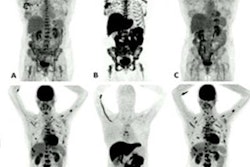

F-18 FES PET images of patients with estrogen receptor positive, progesterone receptor positive, HER2 negative invasive ductal carcinoma. Left panel: Progressive disease seen at the eight-week time point in a patient on sequential therapy. Right panel: Stable disease through all three time points, remaining on study therapy for 6.7 months until disease progression on combined vorinostat aromatase inhibitor therapy. Image courtesy of Lanell M. Petersen, research scientist at the University of Washington Medical Oncology in Seattle.Researchers enrolled 23 ER-positive/HER2-negative breast cancer patients who had previously responded well to endocrine therapy while on an aromatase inhibitor in a study to better understand the effectiveness of this therapy. Eight participants were treated with vorinostat followed by an aromatase inhibitor, and 15 were treated with both at the same time.

After eight weeks, eight patients had stable disease, and six of them remained stable for more than six months. Higher baseline F-18 fluoroestradiol uptake was associated with longer progression-free survival, according to the results.